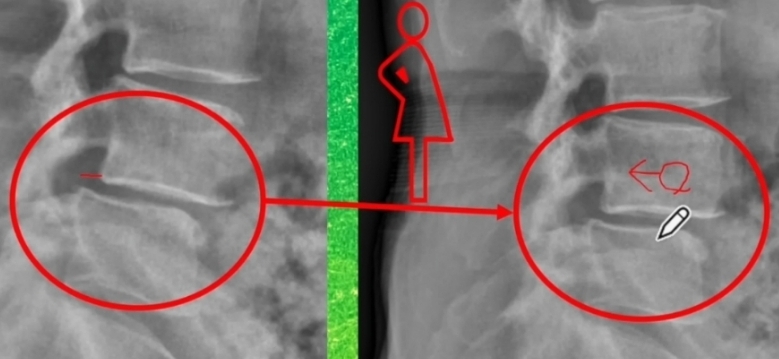

하나의 척추가 인접하는 밑의 척추에 비해 정상적인 정렬을 이루지 못하고 앞으로 빠져있는 상태.